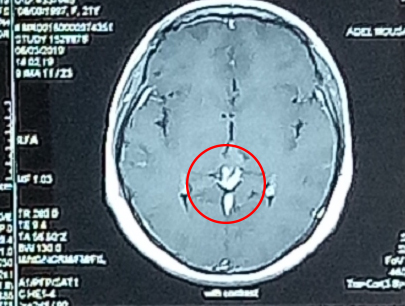

Multiple Metastasis

Radiosurgery adalah tindakan ideal untuk metastasis (anak sebar tumor ganas) ke otak.

Metastasis pada otak dilokalisir dengan baik.

SEBELUM

SESUDAH